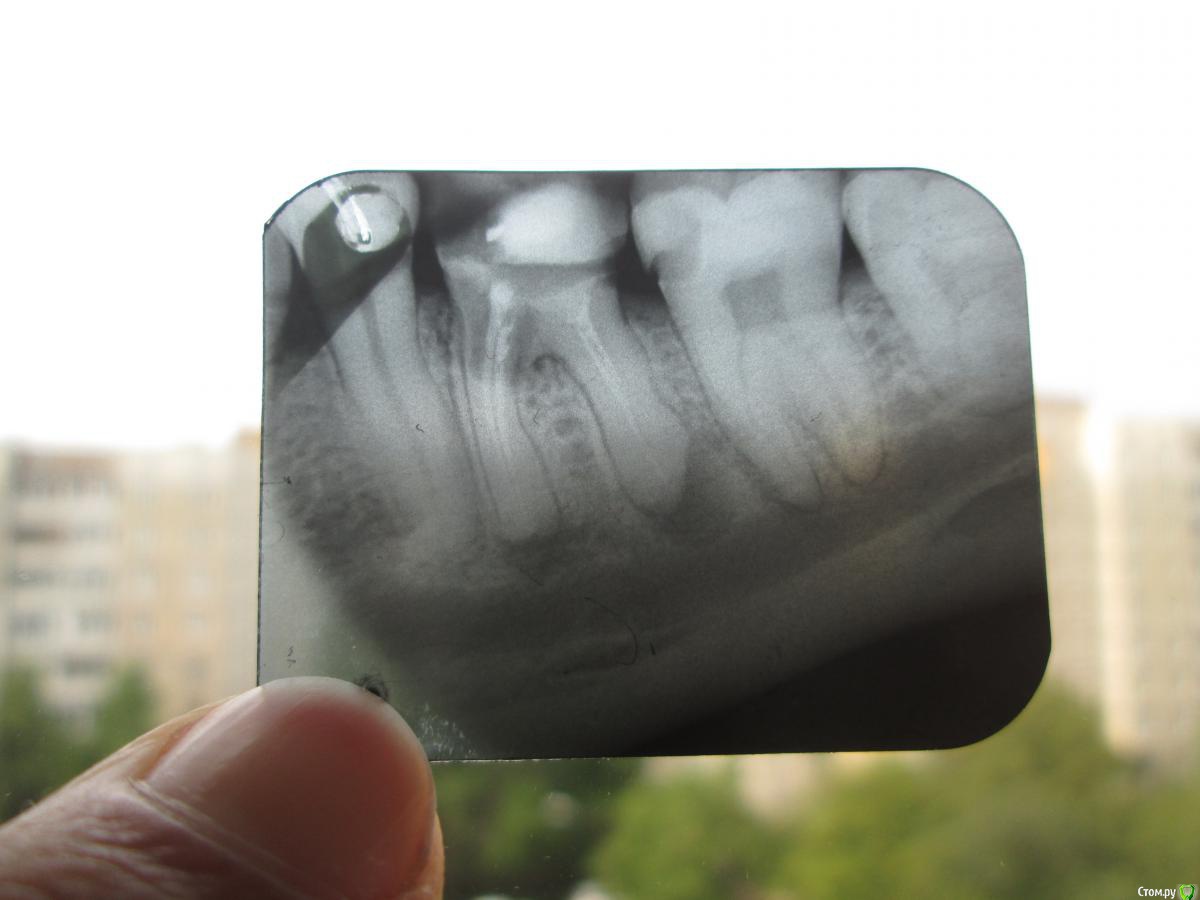

Игорь-32 Опубликовано 20 мая, 2016 Поделиться Опубликовано 20 мая, 2016 (изменено) Добрый день! Форумчане, врачи, прошу вашего совета.Шестой снизу зуб, был запломбирован в примерно в 2006 - 7 году, удалены нервы.Сейчас (2016 г.) рентген-снимок показывает гранулемы под корнями.Врач каналы распломбировать не может, говорит зацементировано намертво, советует удалять зуб, хотя 10 лет не беспокоил.Фото снимка прикладываю (зуб второй слева). Изменено 20 мая, 2016 пользователем Игорь-32 Ссылка на комментарий